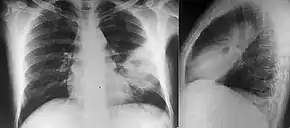

Various imaging modalities can also help with the diagnosis of melioidosis. In acute melioidosis with the spreading of the bacteria through the bloodstream, the chest X-ray shows multifocal nodular lesions. It may also show merging nodules or cavitations. For those with acute melioidosis without the spread to the bloodstream, chest x-ray most commonly shows upper lobe consolidation or cavitations.[10] In chronic melioidosis, the slowly progressing of upper lobe consolidation of the lungs resembles tuberculosis.[10] For abscesses located in other parts of the body apart from the lungs, especially in the liver and spleen, CT scan has higher sensitivity when compared with an ultrasound scan. In liver and splenic abscesses, an ultrasound scan shows "target-like" lesions while CT scan shows "honeycomb sign" (abscess with loculations separated by thin septa) in liver abscesses.[10] For melioidosis involving the brain, MRI have higher sensitivity than a CT scan in diagnosing the lesion. MRI shows ring-enhancing lesions for brain melioidosis.[10]